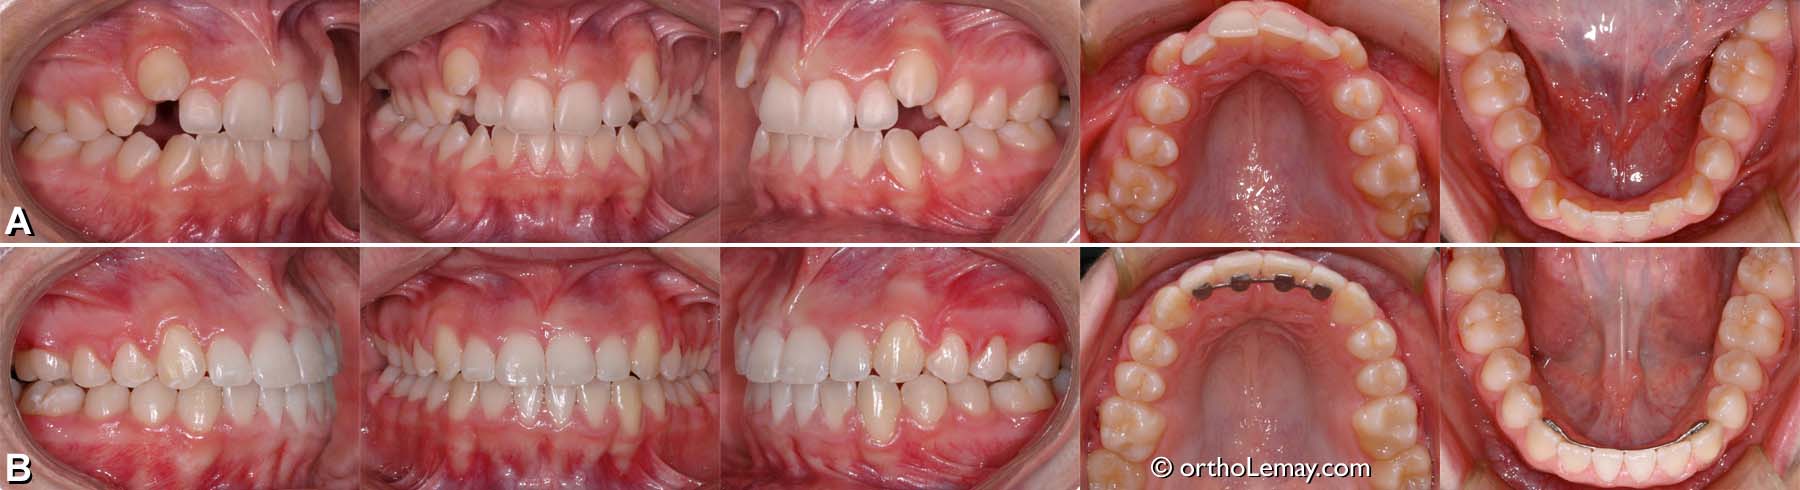

Exemple de traitement de malocclusion classe 1 (19)

Adolescente de 12 ans.

(A) Malocclusion classe 1 avec tendance à la béance postérieure bilatérale et arcade supérieure étroite.

(B) Occlusion après le traitement; de bons contacts postérieurs ont été obtenus pour améliorer la fonction. Les canines sont maintenant fonctionnelles et protégeront davantage les incisives contre l’usure en fonction.